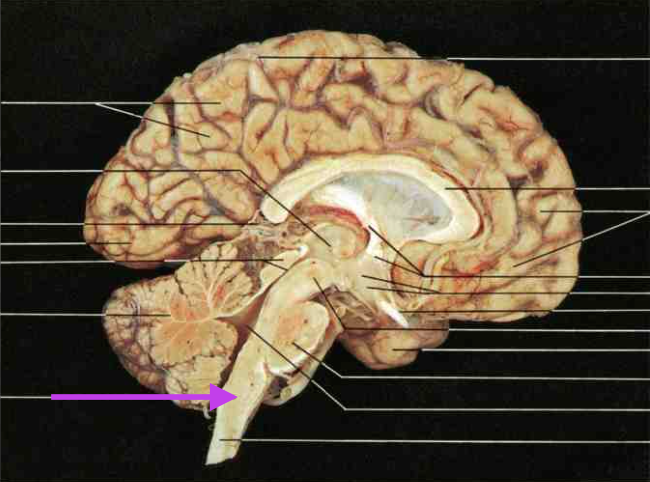

Pons. Section is brain stem.

Medulla oblongata. Section is brain stem.

Fourth ventricle. Section is brain stem.